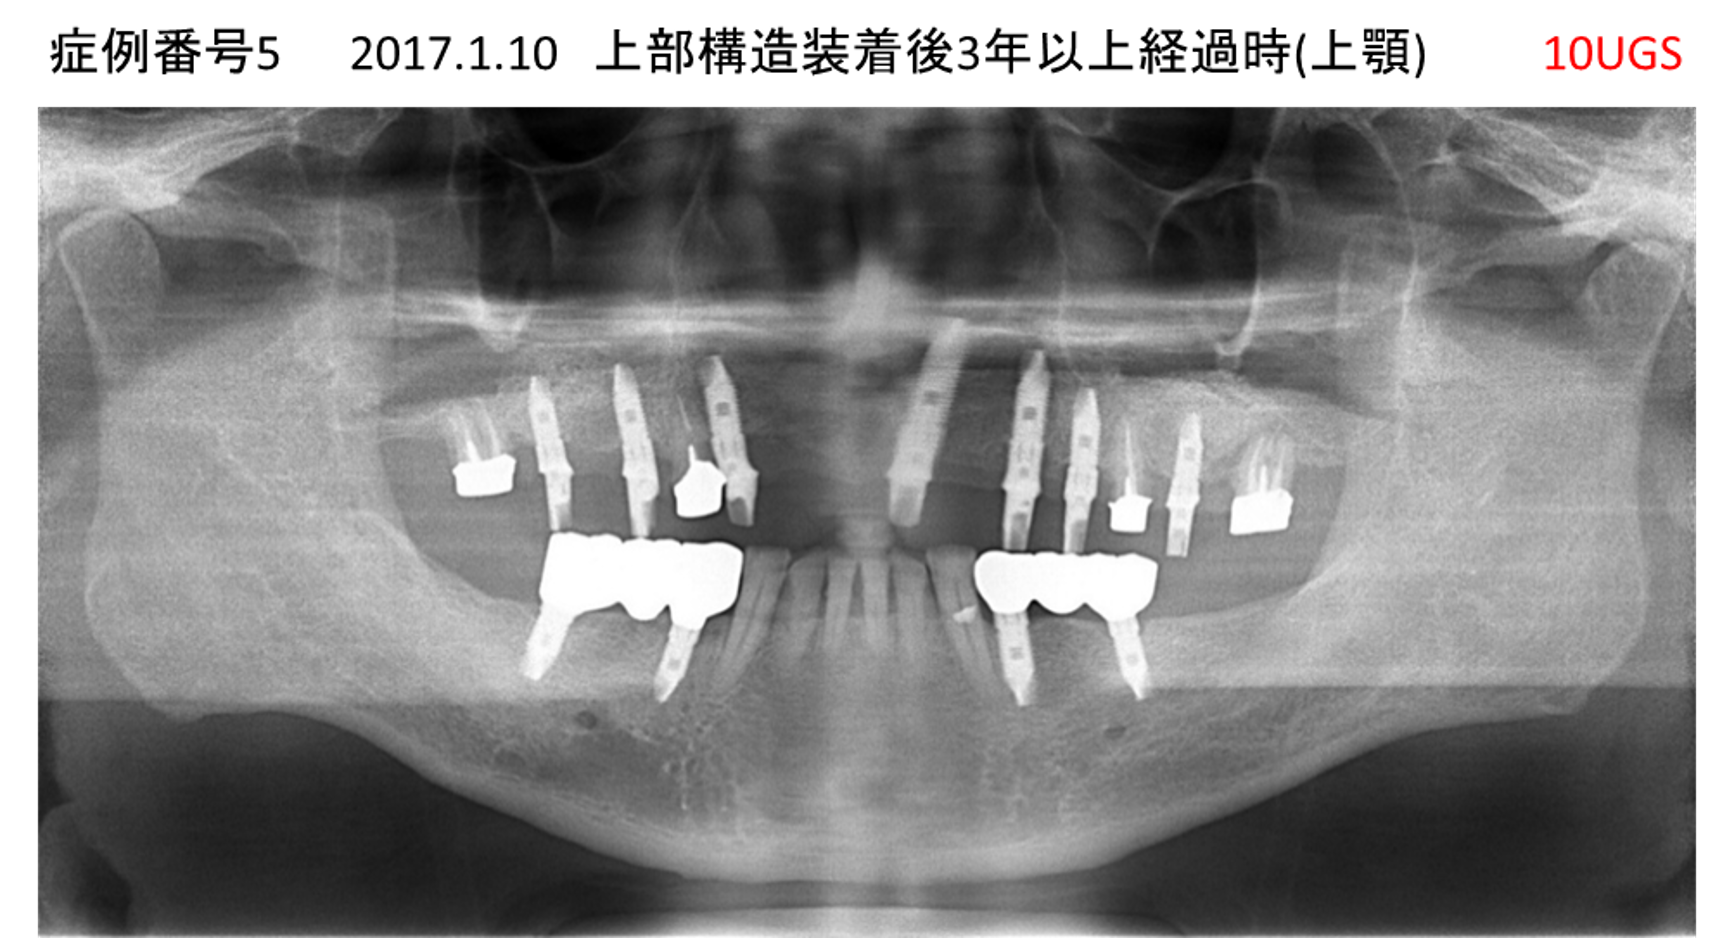

全く噛めない患者様のインプラント症例

| 治療名称 |

インプラントAGC |

| 治療費用 |

860万円+税 |

| 治療期間 |

12か月 |

| 患者さんの症状(主訴) |

全く噛めない、ごはんが後もに食べられるようになりたい、人前で口元を隠したくない |

| 治療内容 |

サイナスリフト、GBR、インプラント、AGC |

| 治療結果 |

しっかり噛めて踏ん張ることができる。食べ物をを選ばなくて済む、何でも食べられる、体重が増えた。見栄えがきれいすぎて自分じゃないみたい |

| 治療の注意点(リスク/副作用) |

インプラントが壊れたら再治療が必要 |